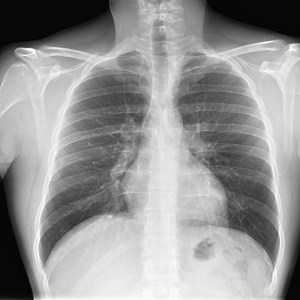

Para empezar, ¿qué ves?

- Comprobar que la placa está bien centrada e inspirada (6 arcos costales anteriores ó 9 posteriores).

- Abdomen y Diafragma

- Partes blandas y estructura ósea.

- Mediastino con silueta cardiaca.

- Parénquimas pulmonares (por separado)

- Comparar un pulmón con otro.

Seguir esta sistemática, dejando el pulmón para el final no nos olvidaremos de lo más importante.

Regla: Acaso Tiene Mucha Patología Pulmonar (Abdomen, Tejidos blandos y hueso, Mediastino, Pulmón por separado, Pulmón bilateral)

Nota: ¡¡¡No olvidar la placa lateral!!! La regla a seguir es la misma. Leer abdomen y diafragma, examinar parte posterior, tejidos blandos y subir por la columna; tráquea y descender por mediastino. Finalmente pulmones.

Solución: Es un estudio Normal. Silueta cardiomediastínica y parénquimas pulmonares sin alteraciones significativas.